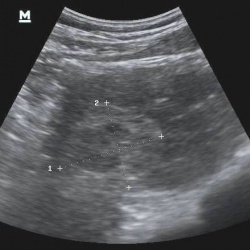

Мужчина, возраст 60 лет. При шёл на обследование брюшной полости. Был направлен дерматологом, так как имеет кожные высыпания, диагноз не ясен. В прошлом, часто находился в африканских странах,...